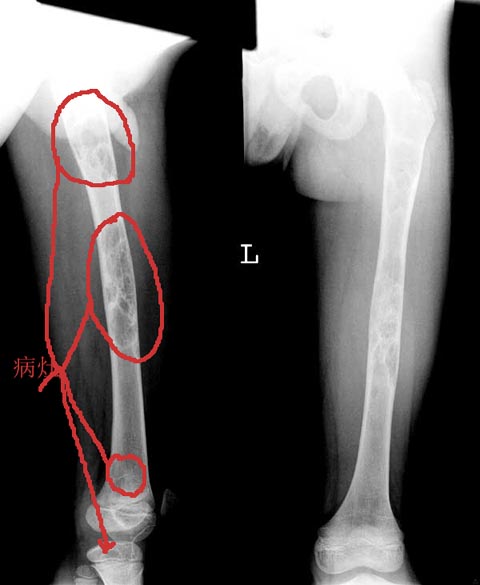

右股骨干病理骨折.

股骨干较大范围膨胀性骨破坏[两处] ,其内见丝瓜瓤改变,皮质变薄,

骨纤维异常增殖征

股骨干较大范围膨胀性骨破坏与骨长轴走行伴病理性骨折,皮质变薄,,其内见丝瓜瓤样与磨玻璃样改变,皮质变薄,又是小儿考虑骨纤维结构不良,骨囊肿待排。

股骨干膨胀性破坏内见丝瓜瓤改变,皮质变薄,还是考虑骨纤

病变范围较大,呈不均匀性膨胀性囊性低密度,且不均匀,内有间隔。考虑:1,骨纤维异常增殖症 2,甲状旁腺机能亢进不排除。[emb18]

股骨干轻度膨胀,内有多个囊状透亮区及磨玻璃样影,右胫骨上端亦有小囊状影。

诊断:骨纤维异常增殖症。

病灶多发,范围较广,呈丝瓜襄样,还是考虑骨纤